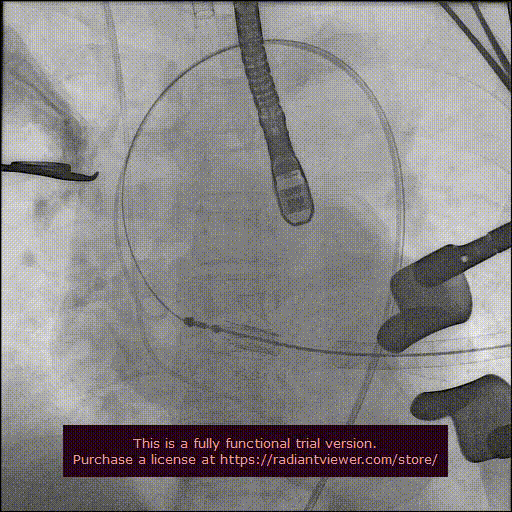

经心尖途径置入 J-Valve 瓣膜输送系统,在升主动脉部打开定位件,调整角度,轻轻向后牵拉输送器使定位件进入主动脉窦内。联合主动脉根部造影和食管超声观看定位件是否定位于窦底,形态随着心脏跳动而自然摆动即可。下降瓣膜至主动脉瓣环内,在主动脉瓣口释放瓣膜支架,此过程无需快速起搏。瓣膜成功释放后移除瓣膜输送系统。行主动脉根部造影及经食管超声检查,对瓣膜功能、位置情况进行术后即刻评估。确认位置良好、功能正常后,移除导丝及输送系统,并收紧心尖荷包缝线打结固定。

定位件入窦

瓣膜降至瓣环平面